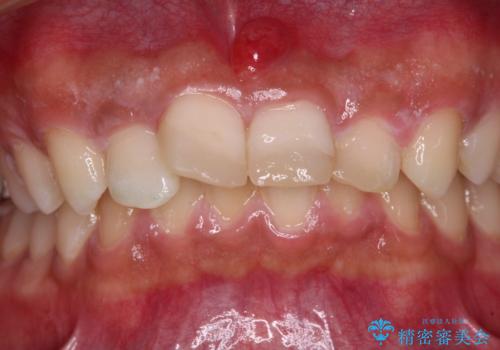

転んでぶつけて抜歯 前歯のオールセラミックブリッジ

- 酒席の後に転倒して前歯を損傷し、応急処置のみを受けてきたとのことで来院された患者様です。

損傷がひどく、前歯4本と広範囲であったため、症状やレントゲン写真、検査結果が一致せず、定期的に経過を見ながら診断していくこととしました。

右側前歯は歯根が短くなり、パンチング状に歯根に透過像が認められたため、予後不良と判断し抜歯することとしました。

当初のレントゲン写真では根尖部に骨透過像が認められた両サイドの2歯は、歯髄の正常な反応が認められたためそのまま保存し、左側前歯は歯髄が失活していたため根管治療を行うこととしました。

抜歯後の欠損部はブリッジにて補綴治療を行うこととしました。

事故直後のレントゲン写真では全ての歯の根尖部に骨透過像が認められましたが、治療後には全ての透過像がなくなっていました。

診断に2-3ヶ月かかりましたが、的確に診断を行うことができました。